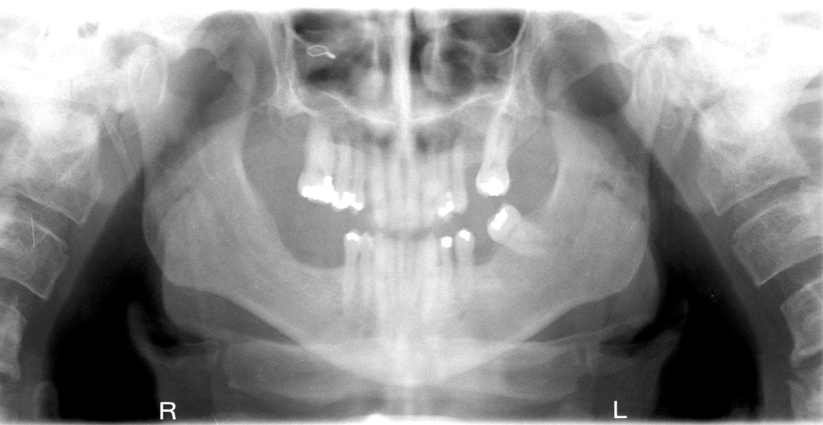

What is wrong with this image?

chin down